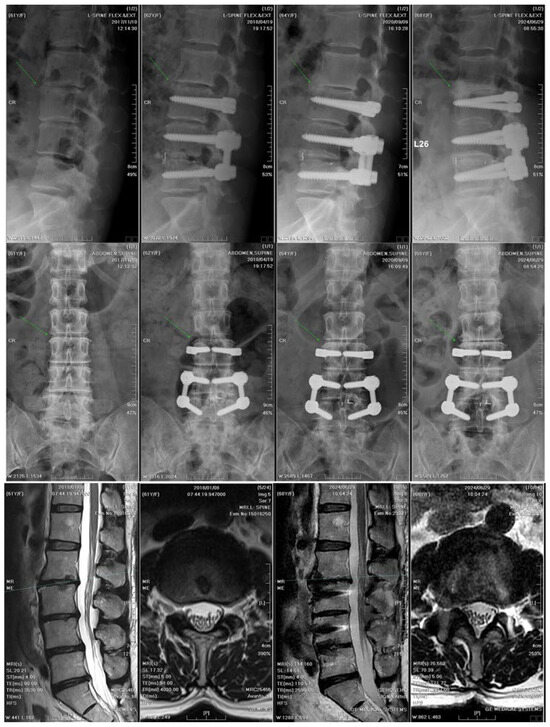

3.5. Analysis of Clinical Cases with L3–L4–L5 Dynamic Hybrid Fixation